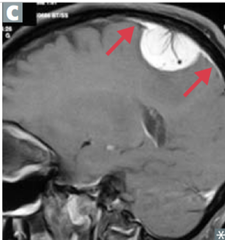

Invasive Ductal Carcinoma

Invasive carcinoma that forms "duct-like" structures...most common 85% Presentation: - rock hard mass that doesn't move - may result in dimpling/retraction at nipple Types: - tubular: well differentiated tubules with no myoepithelial cells - mucinous: abundant extracellular mucus (tumor cells in mucus pool) - medullary: lymphocytes, plasma cells - inflammatory: dermal lymphatic invasion --> inflammation/swelling w/ peau d'orange (can be mistaken for mastitis)